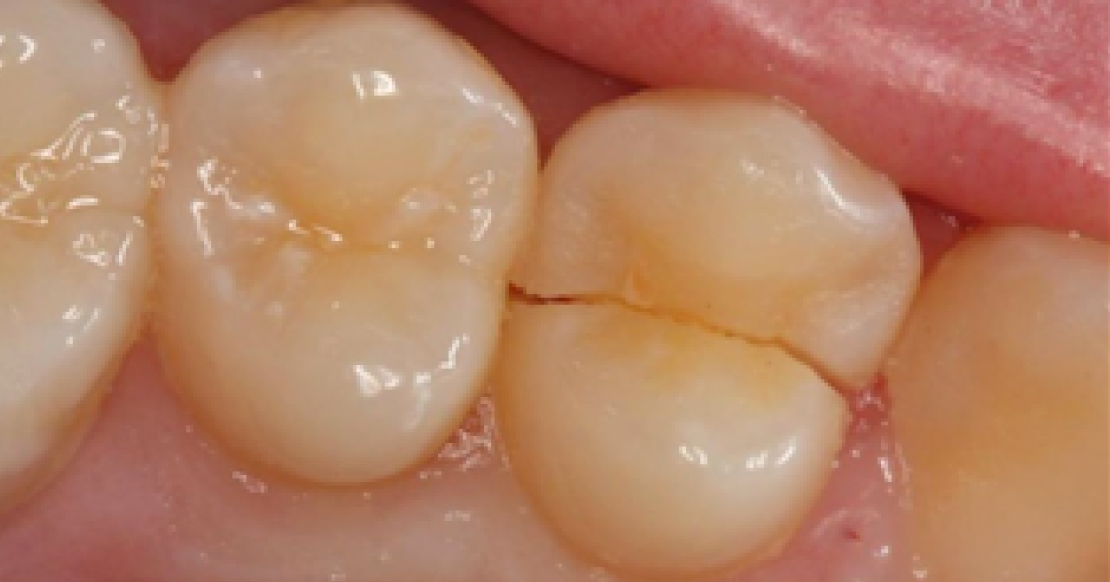

Fracture line cracks penetrate dentin. They may appear as stained lines with no enamel separation or as true splits in enamel. Symptoms may include biting pressure, release pain, and cold sensitivity. Fracture lines in posterior teeth that cross marginal ridges are more concerning than those that remain within the confines of the occlusal surface.

Fracture lines are commonly observed in teeth with extensive restorations, resulting from the weakening of the natural tooth structure. Severity and prognosis cannot be fully determined until pulp testing and definitive excavation are performed.